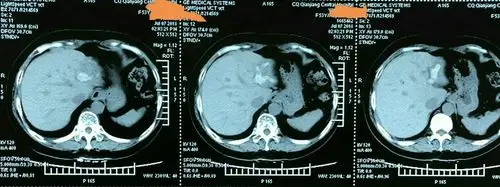

术前ct提示:左肝肝内胆管结石.

这是术前ct提示肝内外胆管结石